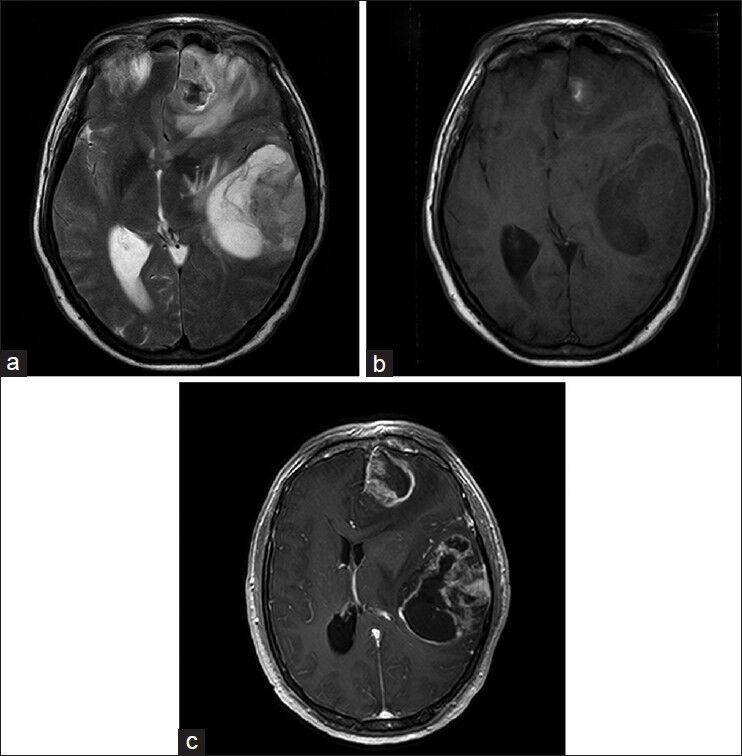

A patient, who presented with a short history of progressive headache and difficulty with memory recall, was found on MRI imaging to have two intracranial lesions. These showed heterogeneous enhancement and were found in the left frontal and left temporal regions. The patient underwent gross total resection of these two lesions which were found to show GBM-O and GBM-PNET differentiations.

一名患者,有进行性头痛和记忆回忆困难的短病史,MRI成像发现有两个颅内病变。这些病变表现为不均匀强化,位于左侧额叶和左侧颞叶区域。患者接受了这两个病变的全切除,发现病变显示GBM-O和GBM-PNET分化。